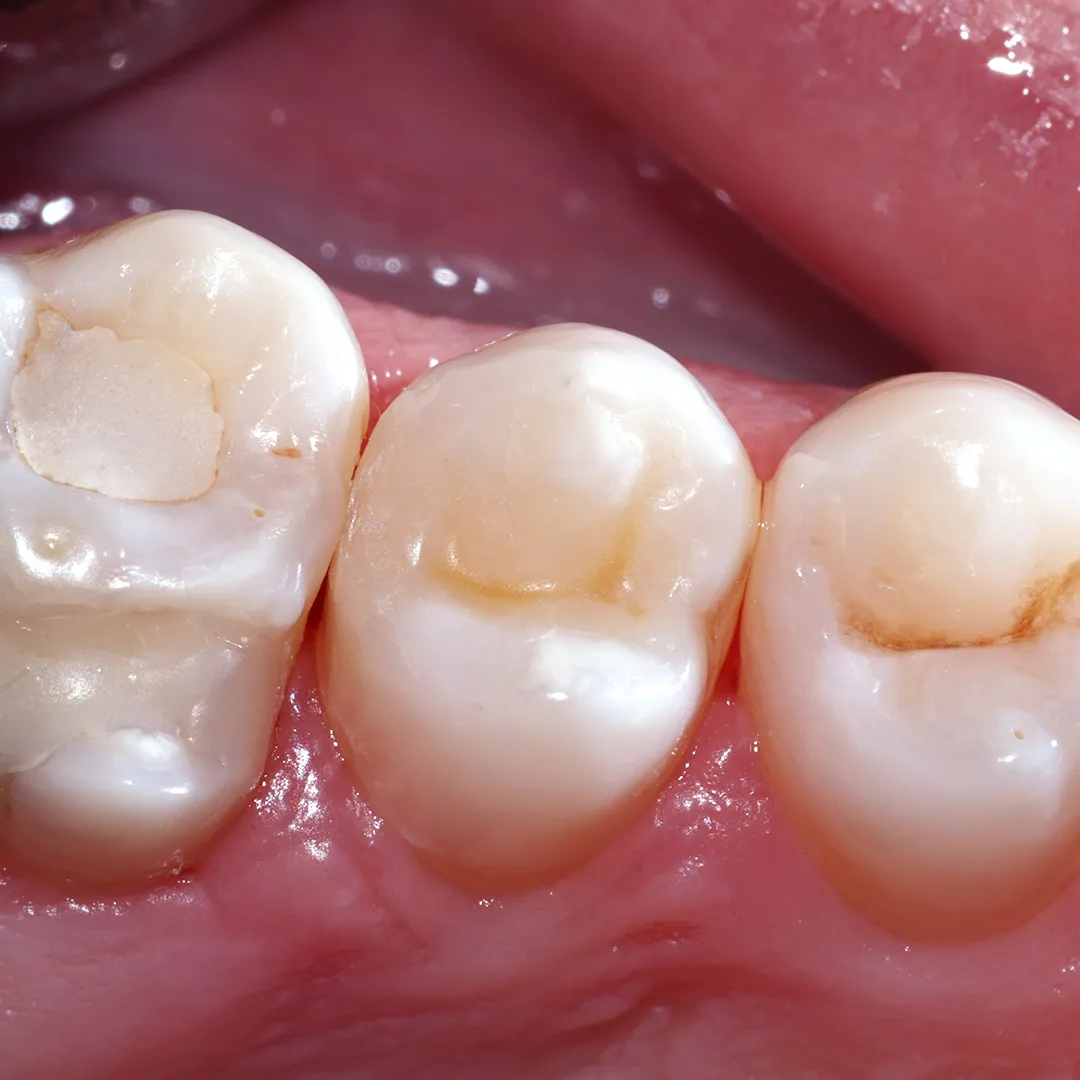

До и после лечения

Пациент обратился в «Стоматологию Комфорта» с жалобами на постоянное застревание пищи между зубами верхней челюсти с правой стороны. После осмотре стоматолог Галухина Карина Николаевна обнаружила кариес дентина зуба 1.6 и поставила соответствующий диагноз. Врачом было принято решение о проведении лечения с применением фотополимерного композита Estelite.